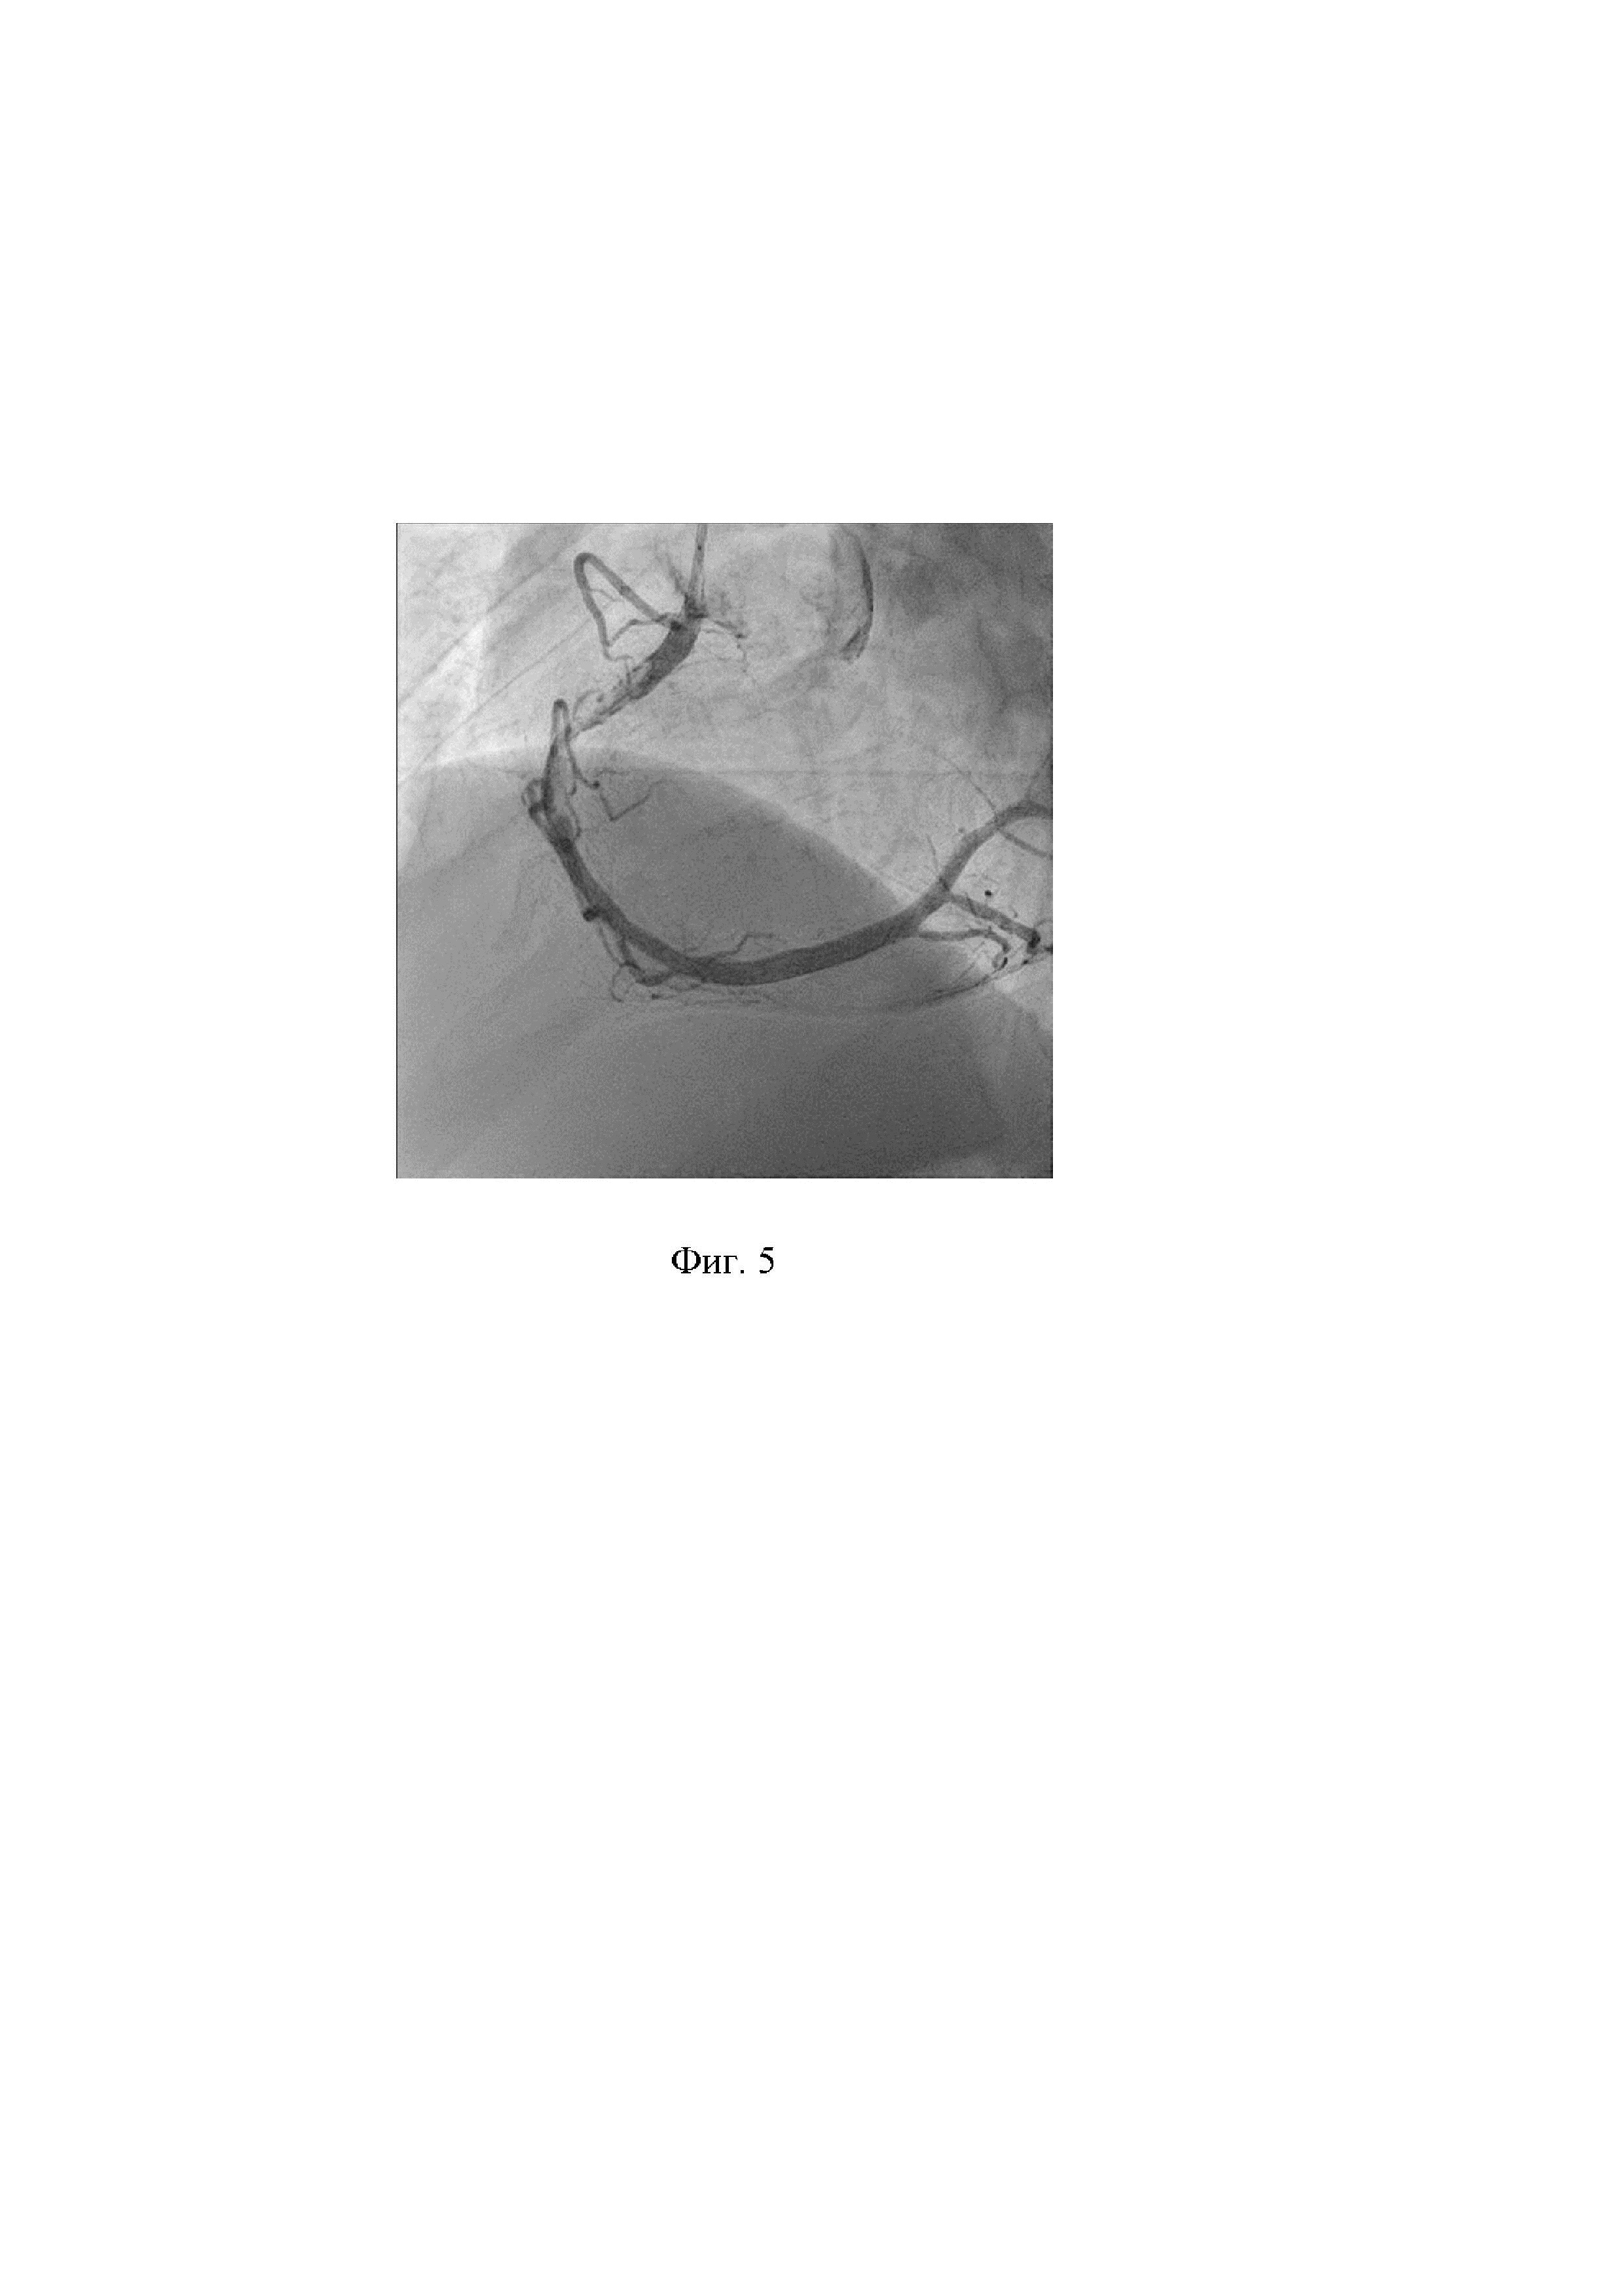

10. Выполнена контрольная коронарография. Проведен анализ полученных результатов - восстановлен антеградный кровоток TIMI III по ПКА без признаков дистальной эмболизации и интраоперационных осложнений, связанных с применением способа. Признаки сохраняющегося пристеночного тромбоза. Стеноз 50% в средней трети задней межжелудочковой ветви (ЗМЖВ). На фигуре 5 показано состояние ПКА после выполнения аспирационной тромбэмболэктомии проводниковым катетером. В зону остаточного стеноза и пристеночного тромбоза в ПКА имплантирован коронарный стент ∅4,0x33 мм. На фигуре 6 показано состояние ПКА после имплантации коронарного стента.